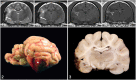

Meningioangiomatosis (MA) is a rare proliferative meningovascular entity that has been described mainly in humans and dogs. Here we describe MA in a 13-y-old spayed female domestic shorthaired cat that died 5 d after acute change in behavior, open-mouth breathing, seizures, hyperthermia, and inability to walk. On MRI, the lesion appeared predominantly as extraparenchymal hemorrhage. Autopsy changes consisted of a dark-red, hemorrhagic plaque that expanded the leptomeninges and outer neuroparenchyma of the right piriform and temporal telencephalic lobes, chalky white nodules in the peripancreatic fat, and yellow fluid in the abdomen. Histologically, the lesion in the brain consisted of leptomeningeal thickening by spindle cells that effaced the subarachnoid spaces and extended perivascularly into the underlying cerebral cortex. Spindle cells were arranged as streams or whorls around blood vessels, and had slender eosinophilic cytoplasm and elongated nuclei with coarsely stippled chromatin and 1 or 2 distinct nucleoli. There was extensive hemorrhage, clusters of hemosiderin-laden macrophages, and mineralization throughout. Spindle cells had positive immunolabeling for vimentin. A striking MRI and gross feature in our case was the extensive hemorrhage associated with the MA lesion. Additional findings included suppurative pancreatitis with peritonitis and supraspinatus myonecrosis.